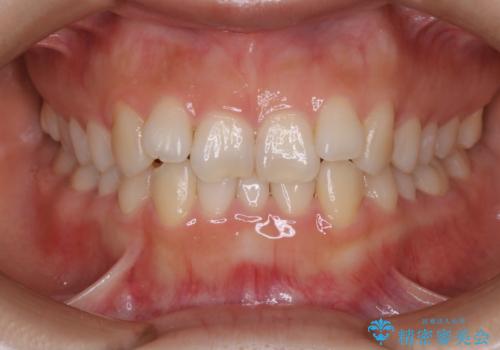

八重歯でがたつきは重度でしたが、きれいな歯並びにすることができました。

がたつきだけでなく、奥歯の噛み合わせのずれの調整もしっかり行いました。

歯並びがきれいになることで、虫歯予防や歯周病予防にもつながります。